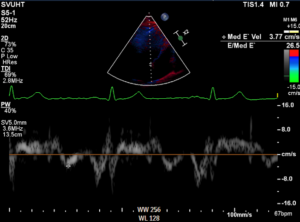

Mitral inflow and mitral TDI data are shown below

Findings are suggestive of: